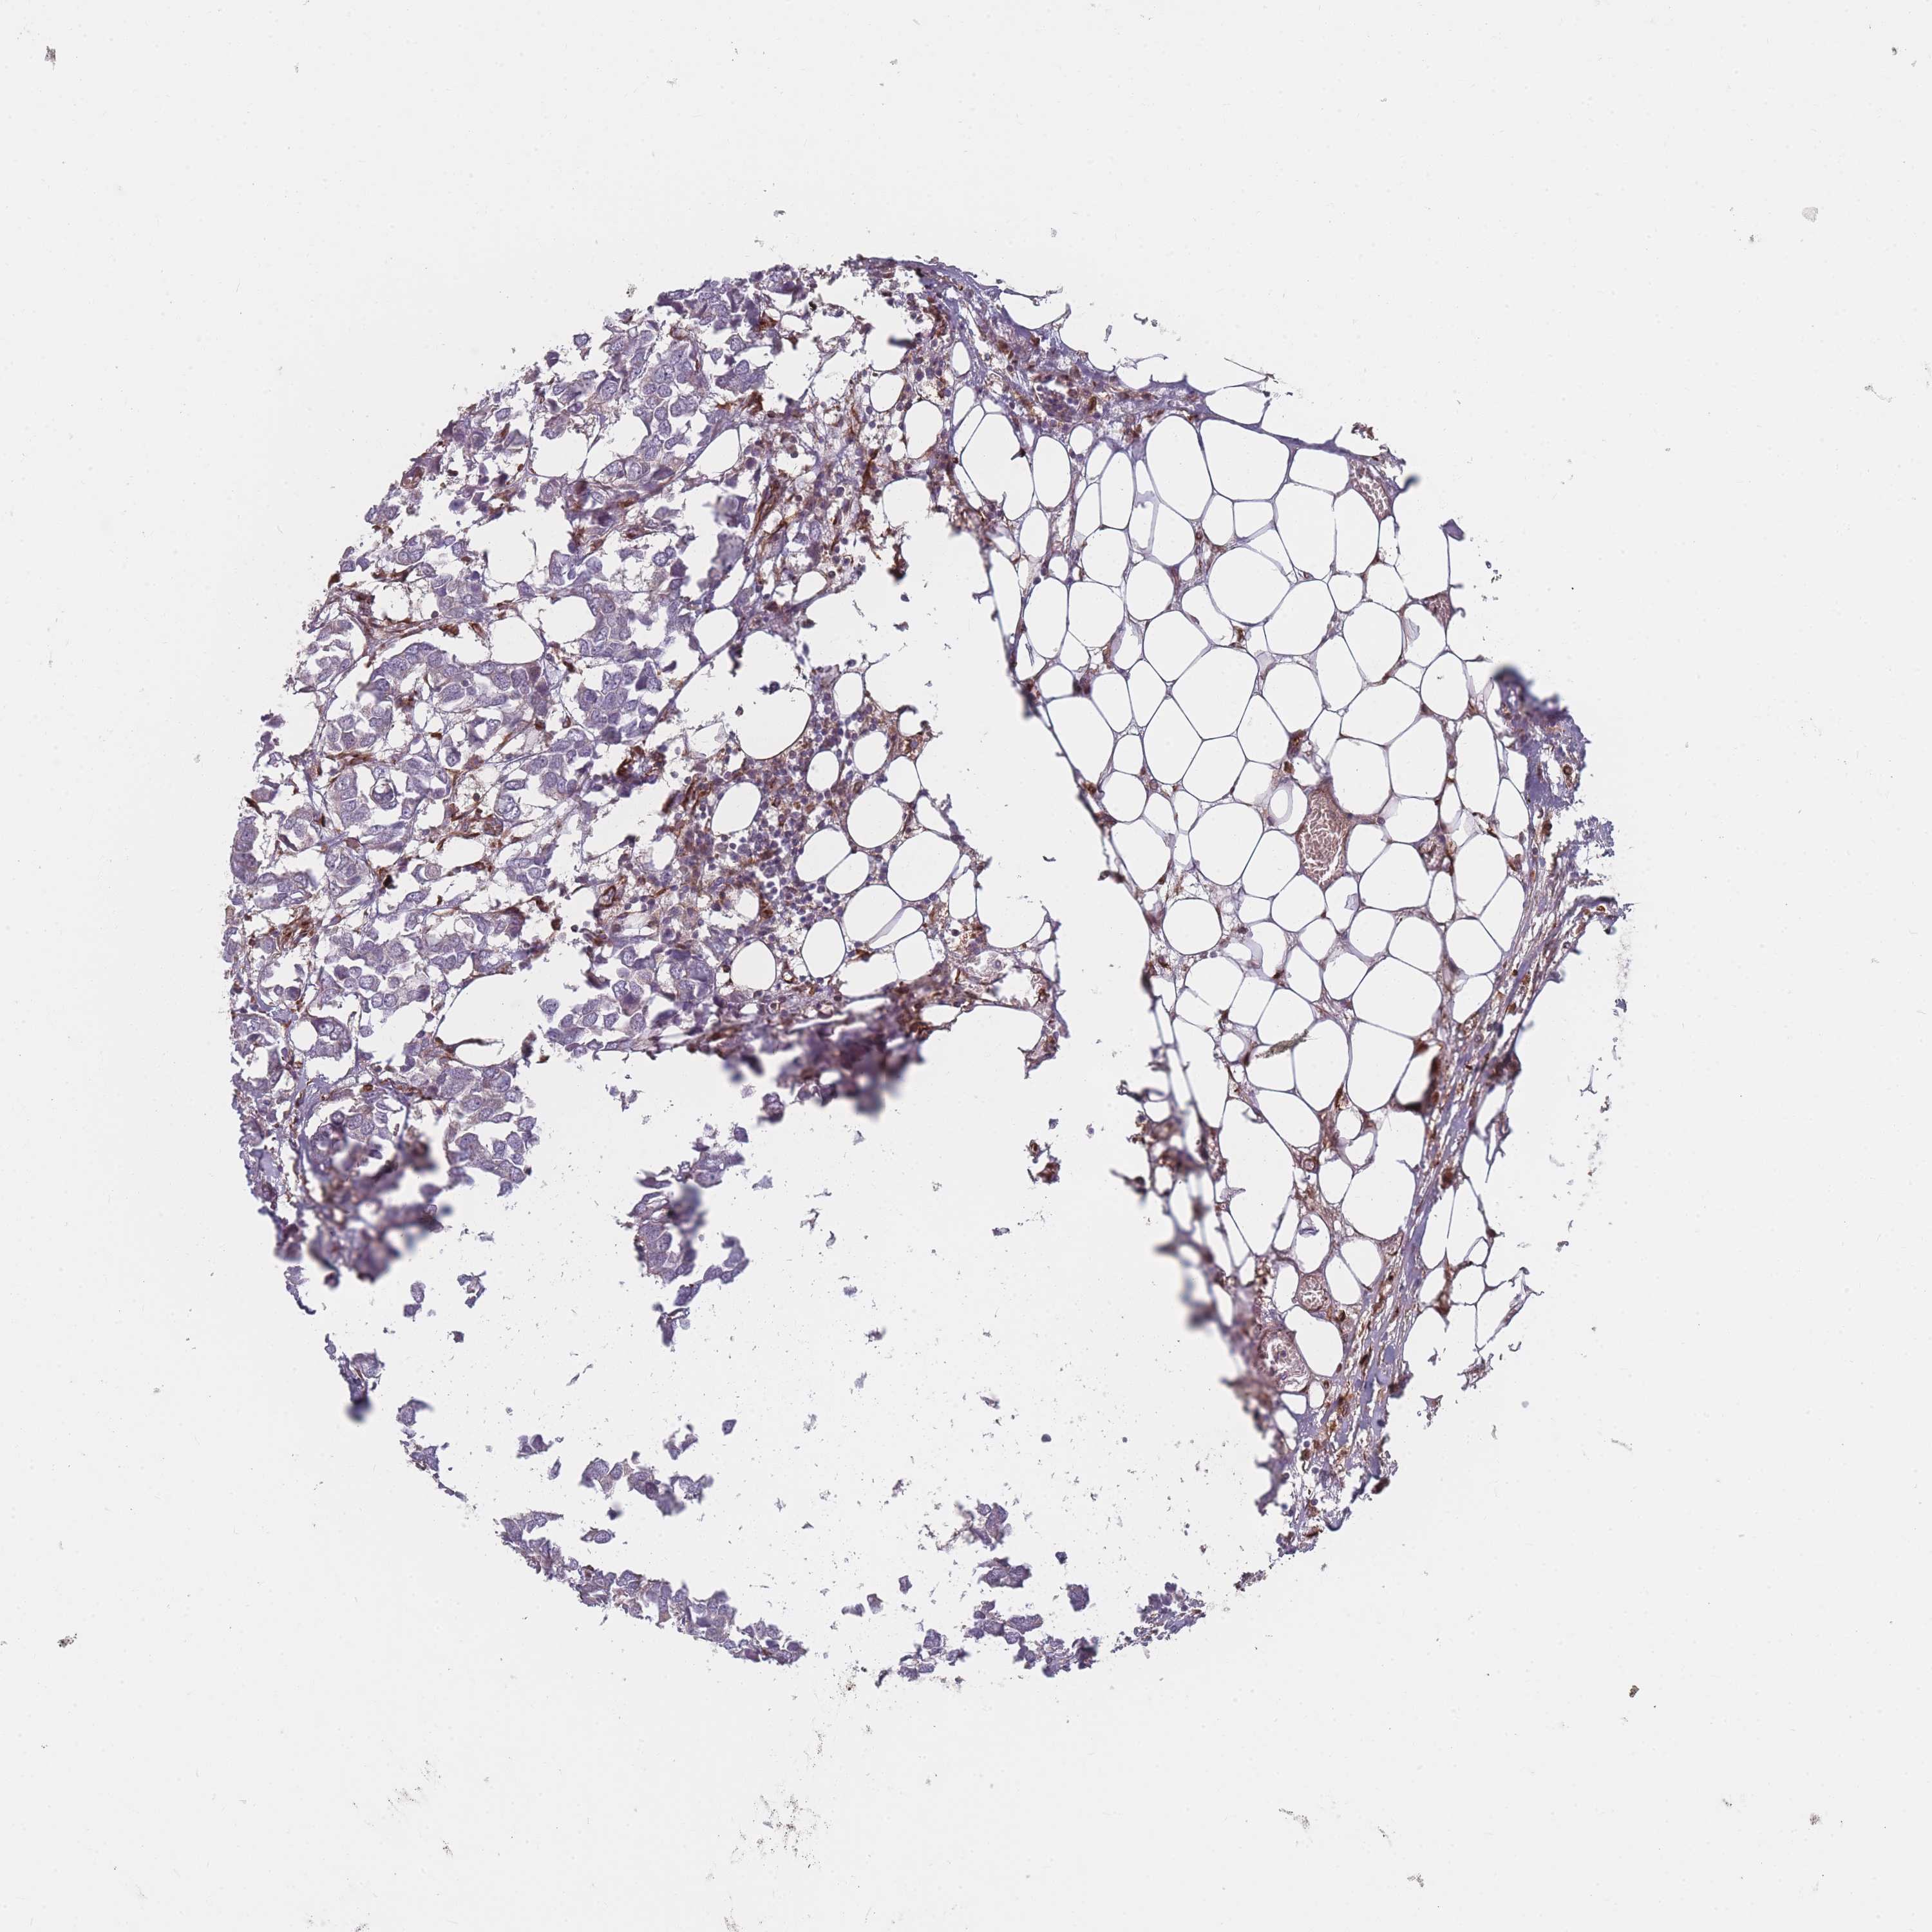

Breast cancer

Human cancer